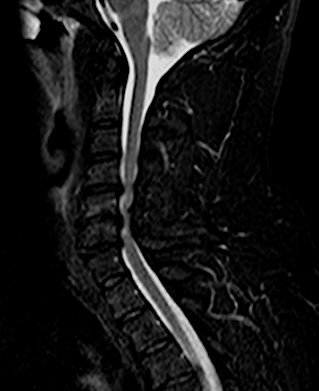

El paciente presentó a las 24horas un agravamiento de la paresia C7 derecha indolora, sin cambios en el puntaje (EMS) de su mielopatía, por lo que se decidió realizar una RM cervical urgente.

El resultado de la RM cervical planteaba dudas si era necesario o mandatorio realizar una descompresión posterior complementaria. Sin embargo, los parámetros clínicos no sugerían una compresión medular: la evolución lenta a la mejoría de su paresia, la ausencia de progresión de su mielopatía y la ausencia de dolor resultaron determinantes para que se adoptara una actitud conservadora. El paciente fue dado de alta (en plena pandemia de covid) y la evolución fue buena a pesar de que no pudo completar la rehabilitación. Se realizó nueva RM y RX cervical a los seis meses que resultó mucho más concluyente.

RM postoperatorio